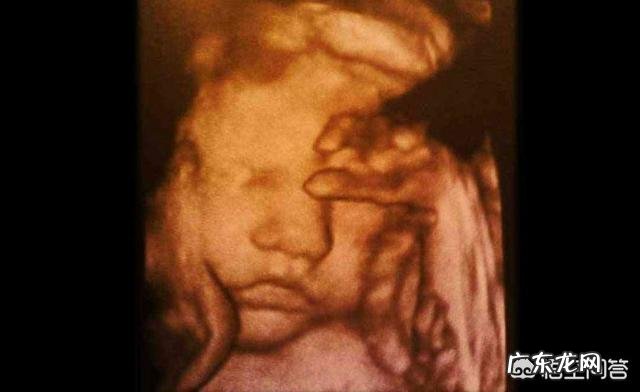

怀孕八个月时,胎儿是什么样的呢?孕8个月也就是29~32周的这个阶段 。

宝宝的变化:这个时候宝宝身长40厘米左右,体重大约1500~1800克,宝宝的身体开始堆积皮下脂肪,身体变得圆润起来,皱纹也开始慢慢消失了,宝宝的肺部和胃肠功能也接近成熟了,能够分泌消化液 。

孕29周:宝宝的体积就像一个茄子一样,头和身体比例已经协调,宝宝的眼睛已经可以转动了,宝宝对光线对声音和味道的感觉更强了 。

孕30周:宝宝的体积就像一个木瓜一样,脑和肺继续发育,头发也变得更密了,眼睛可以睁合了,宝宝的骨骼也开始变硬了,脚趾也在生长 。

孕31周:宝宝的体积就像花椰菜一样,宝宝的脑和肺进入到了发育最后冲刺阶段,宝宝的眼睛变化明显,可以辨别明暗 。

孕32周:宝宝的体积就像一个椰子,这个时期宝宝还是热衷于睁眼和闭眼的小游戏,这个时候宝宝的内脏器官已经发育成熟了,脚趾甲和头发也长的差不多了,胎位也开始固定了 。